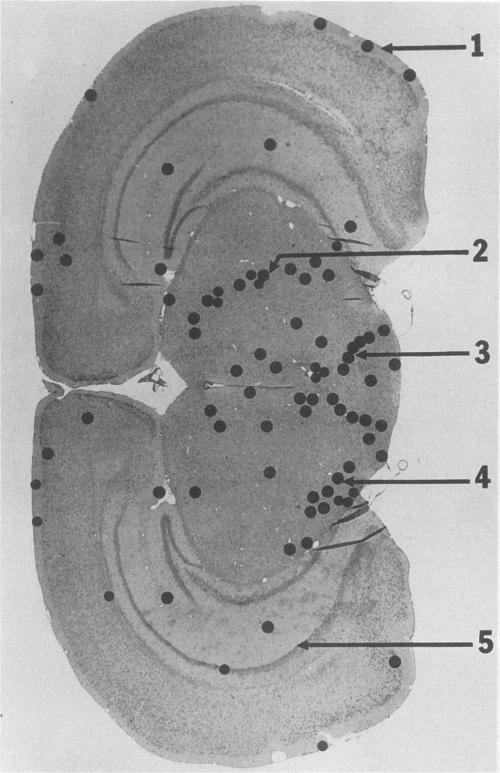

The attachment to and penetration of endothelial cells in the pons and midbrain (especially the substantia nigra) regions of the brains of BALB/c mice by log-phase Nocardia asteroides GUH-2 cells were determined by both scanning and transmission electron microscopic analysis. Within 15 min after exposure, the nocardiae attached to the surface of the endothelial cell membrane. This attachment occurred primarily at the growing tip of the nocardial filament, and the outermost layer of the nocardial cell wall had regions (electron-dense areas) that bound firmly to the cytoplasmic membrane of the host cell. There appeared to be specificity for this binding localized within the capillaries and arterioles because some regions had large numbers of bacteria bound, whereas adjacent areas had no bacterial cells. Nocardial filaments that attached by the apex induced a cuplike deformation of the endothelial cell membrane. This was followed by a rapid penetration of the endothelial cell so that within 25 min many of the bacteria were internalized within the host cell. These internalized bacteria remained within vesicles, and there was no ultrastructural evidence of damage to the nocardial cell during this process. Heat-killed GUH-2 cells still attached to endothelial surfaces (at a reduced frequency), but they did not penetrate into the endothelial cell. These data suggest that brain-invasive nocardiae possess both an adhesin for attachment to the membrane of endothelial cells and an invasion factor that promotes nocardial penetration of these cells.